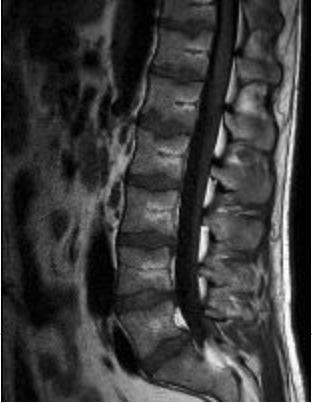

| SAG | T1 | YES | YES | Cover from T12 to S1. |

| SAG | T2 | YES | YES | Cover from T12 to S1. |

- You can change the number of slices, TR, FoV, etc. to get scan into a single acquisition.

- DO NOT CHANGE SLICE THICKNESS OR GAP.